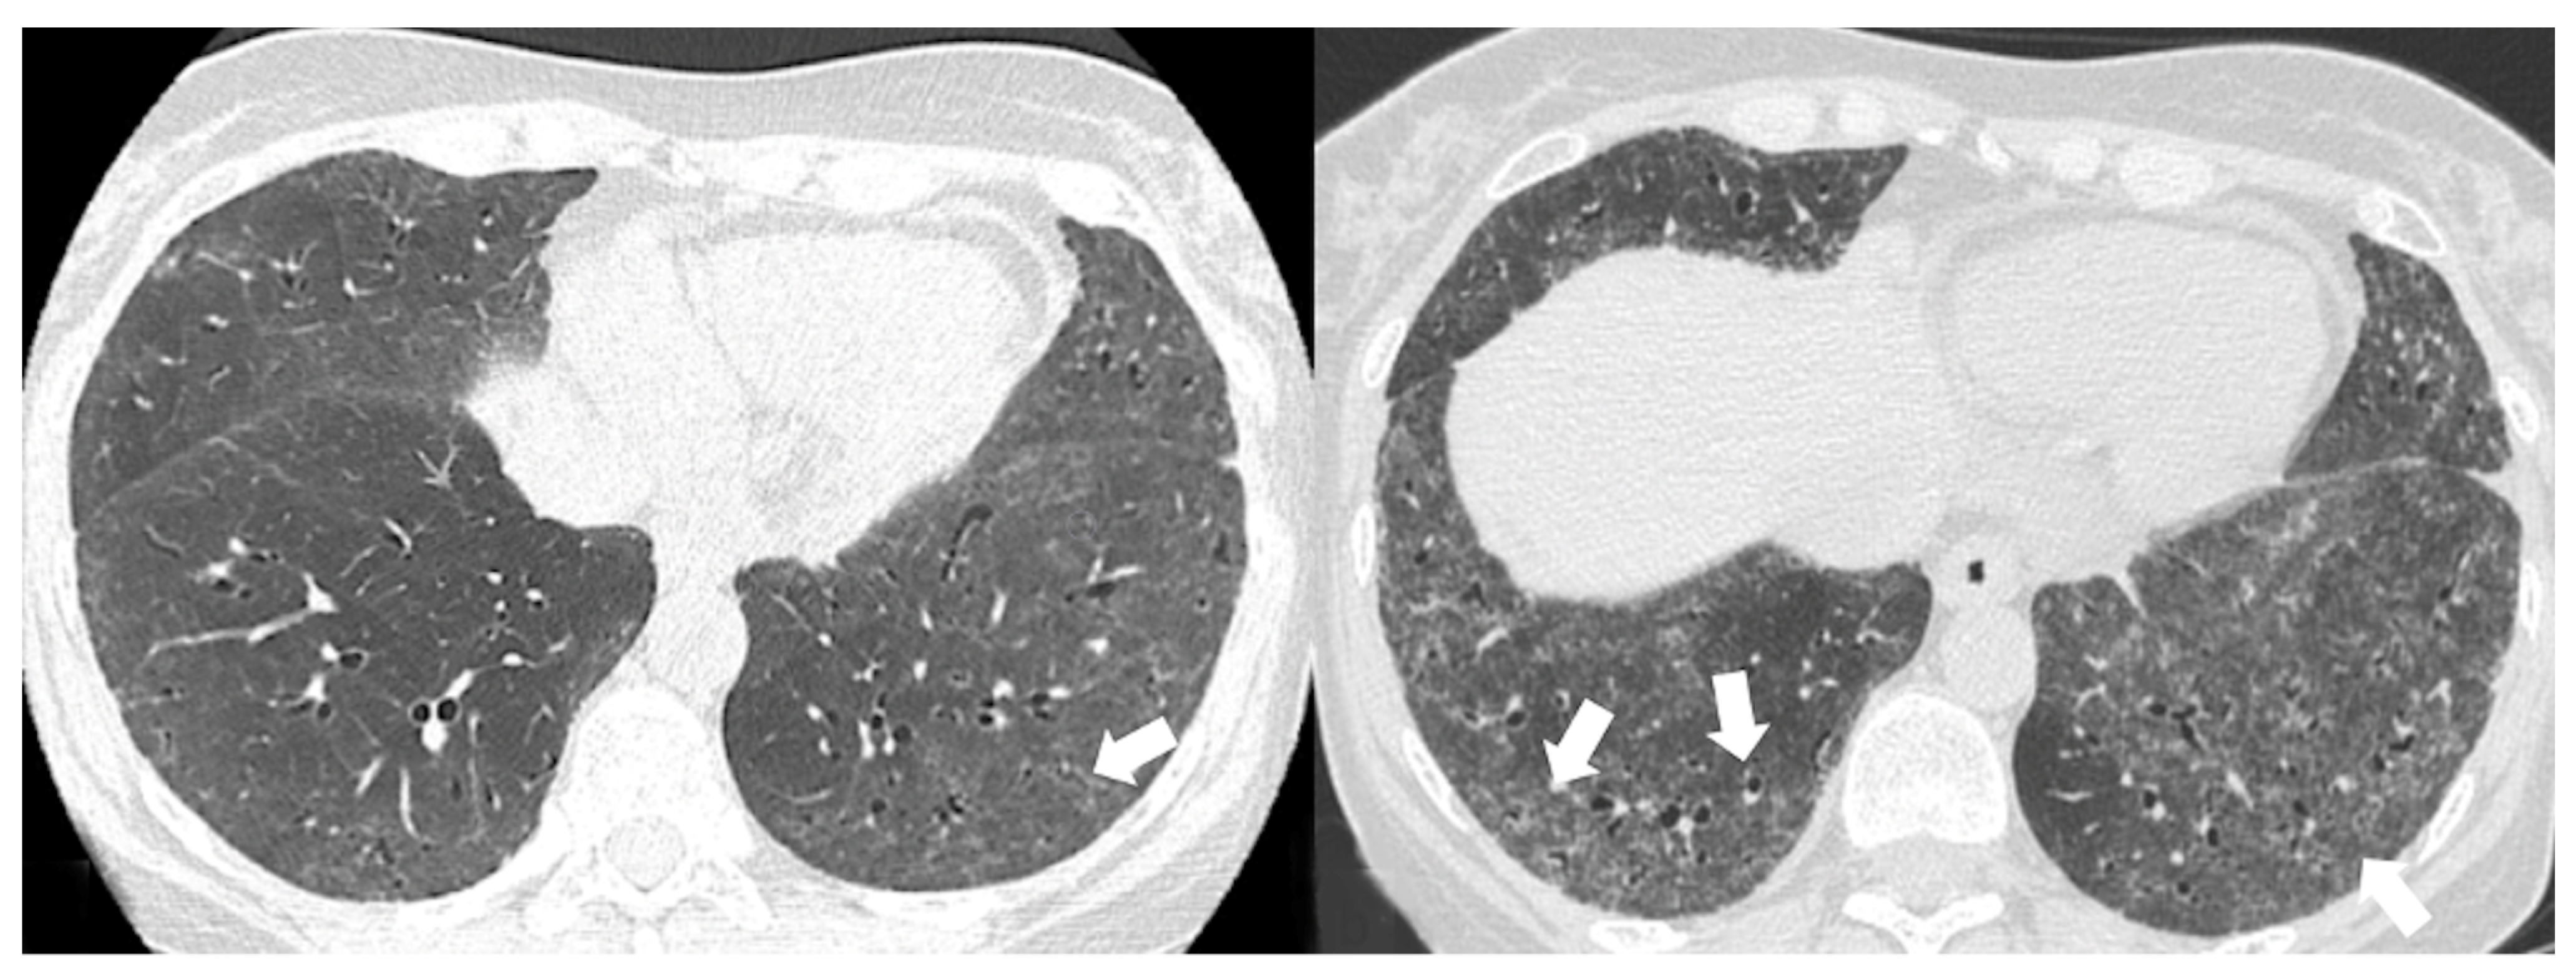

4.2.2. HRCT Findings of Patients with Anti-MDA-5 Abs

| Lesions | GGO, reticulations, consolidations | consolidations, GGOs | |

| Distribution | Homogeneous; lower lung lobes, along bronchovascular bundles and lung periphery; loss of volume of lower lobes | Patchy; peripheral lower lobes or along the bronchovascular bundles | |

| CT pattern | NSIP OP NSIP-OP UIP DAD-unclassifiable | 50% 20% 25% 10% +/− | 20% 50% 25% <5% ++ |